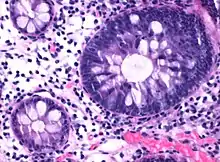

| Micrograph of hyperplastic polyp | |

Histopathology

Histopathologically, there are two main types of hyperplastic polyps, which have genetic differences, as well as different histologic structure, but no significant differences clinically.[4] The two main types of hyperplastic polyps are microvesicular mucin-rich type and goblet cell-rich type.[1] A mucin-poor type with eosinophilic cytoplasm, which is rare, was previously described.[4] However, the mucin poor type is no longer considered a distinct subtype.[1]

Mucin-rich type

The luminal portion has a serrated ("saw tooth") appearance formed by tufts or folds of abundant apical cytoplasm. It contains glands with star-shaped lumina.[4] There are crypts that are elongated but straight, narrow and hyperchromatic at the base. All crypts reach to the muscularis mucosae.[4] The basement membrane is frequently thickened.[4]

Goblet cell-rich type

Elongated, fat crypts and little to no serration. Therefore, they may not be obvious without comparing to adjacent normal intestinal wall.[4]

They are filled with goblet cells, extending to surface, which commonly has a tufted appearance.[4]

Nuclei are small, regular, round and basal in the luminal half of the crypts, most reliably evaluated near the luminal surface.[4]

There are proliferative changes at the base of crypts, where nuclei are enlarged, the nucleus/cytoplasm ratio is elevated.[4]